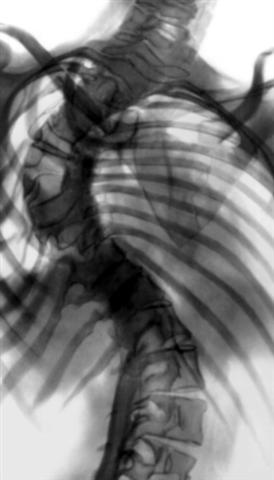

Рис. 18б). Рентгенограмма позвоночника (прямая проекция) при правостороннем грудном сколиозе IV степени после частичной коррекции деформации и заднего спондилодеза.